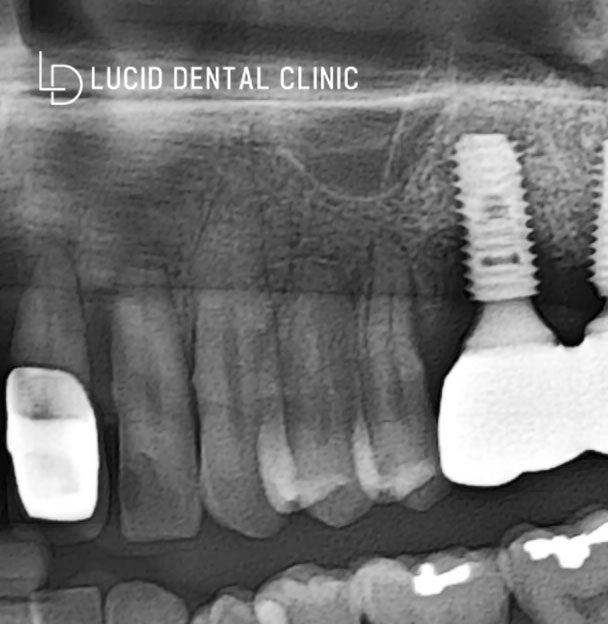

- 세 번째 위 오른쪽 어금니 (대구치)

사진을 보면 아실 수 있는 것처럼

현재 구치부 치아가 없었습니다.

그런데 또 하나 문제가 있었는데요

사진을 보시면 픽스처가

단단히 뼈에 잘 유착이 돼야 되는데

검하고 둥그런 부위가 관찰이 되고 있습니다.

이것을 '상악동'이라 부르는데,

대구치 부위 식립을 하려면

그 부분을 거상하는 시술을 통하여

비어 있는 공간을 위로 올리고

그 사이에 뼈 이식을 통해 픽스처가

단단하게 유착될 수 있도록 하는 방법을

같이 진행해야 됩니다.

✔️ 아무래도 위쪽 같은 경우는

하악 보다 해부학적 구조가 있기 때문에

비용도 많이 들어 시간이 더 오래 걸리고

어려운 케이스에 속하기도 합니다.